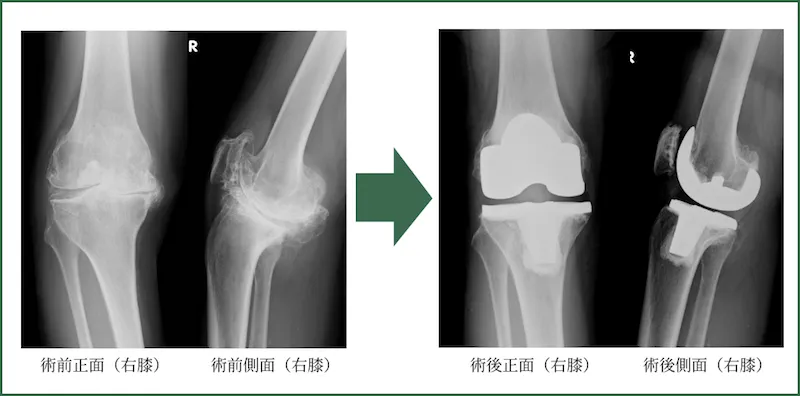

人工膝関節置換術

(Total knee arthroplasty/ Unicompartmental knee arthroplasty)

全身シールド装置(サージカルヘルメット)を使用して、感染については十分にケアして行っております。また両側症例については両側を一期的に行います。

入院期間は、両側も片側も差はなく約2週間です。退院の目安は、階段昇降が自立しておりT字杖歩行が可能な状態です。要するに自分の身のまわりのことができる状態です。術後1ヵ月程度は2回/週、術後4ヵ月程度は1回/週、それ以降、状態に応じて隔週ごと、月ごとのリハビリ通院を要します。スポーツについては、ジョギングやマラソン以外は許容しております。実際、テニス、卓球、バドミントン、登山など行っている方は多いです。よく患者さんに「どのくらいもちますか?」と聞かれることがありますが、我々の行った手術で今の所壊れてしまった(緩くなった)膝は1例もありませんので、「何とも言えないですが20~30年はもつでしょう」とお伝えしております。

よく患者さんに「どのくらいもちますか?」と聞かれることがありますが、我々の行った手術で今の所壊れてしまった(緩くなった)膝は1例もありませんので、「何とも言えないですが20~30年はもつでしょう」とお伝えしております。